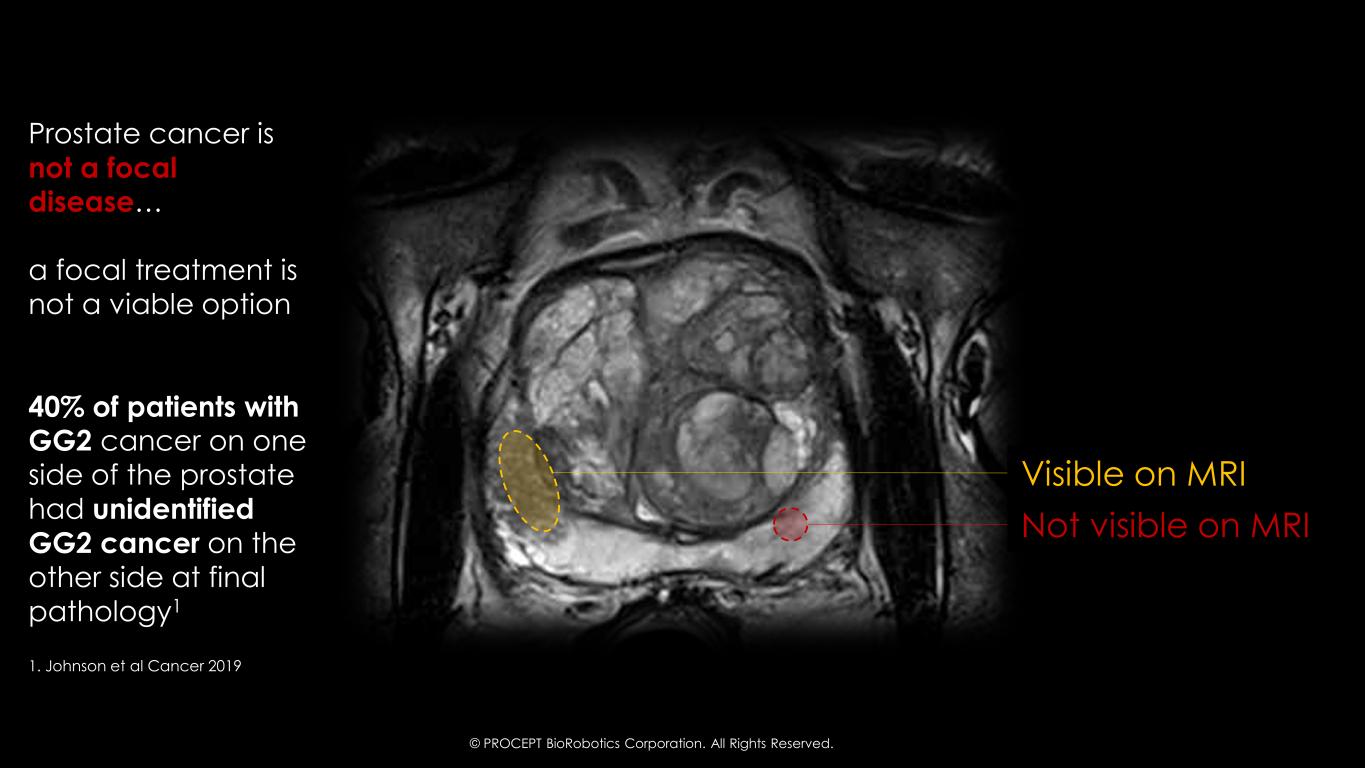

32 Visible on MRI Not visible on MRI 1. Johnson et al Cancer 2019 Prostate cancer is not a focal disease… a focal treatment is not a viable option 40% of patients with GG2 cancer on one side of the prostate had unidentified GG2 cancer on the other side at final pathology1 © PROCEPT BioRobotics Corporation. All Rights Reserved.

39 Diagnostic Uncertainty of Prostate Cancer is Substantial Prostate Cancer is a Multi-Focal Disease1 1 More cancer is often found, making focal therapy less effective1 mpMRI Guided Biopsy is Best Diagnostic - But is Not Perfect 2 40% of unilaterally diagnosed GG2 is actually bilateral2 3 Surveillance studies show ~30% upgrade rate at first biopsy3 4 Focal studies for intermediate risk have consistent ~33% failure rate5-11 1. Iczkowski et al J Urol 2009 2. Adhoot et al NEJM 2020; 3. Johnson et al Cancer 2019. 4. Stavrinides et al Eur Urol 2020 5. Mortezavi et al J Urol 2019; 6. Abreu et al J Urol 2020; 7. Nahar et al J Urol 2020; 8. Ehadie et al 2022; 8. Wysock et al J Urol 2023: 9. Zhu et al E Urol Open 2023; 10. Dixon et al J Endo 2023; 11. Ajami et al Urol Oncol 2024 5 Diagnostic uncertainty supports whole-gland treatments, but they have high morbidity © PROCEPT BioRobotics Corporation. All Rights Reserved.

54 Prostate Cancer is a Not A Focal Disease MISCONCEPTION Aquablation Therapy is Focal Therapy… Aquablation Therapy results in a Near Total Resection of the prostate 1 Waterjet has access to Transitional & Peripheral Zone 2 Ability to resect >95% of all prostate tissue 3 Near Total Resection preserves prostate capsule, resulting in better safety outcomes 40% of Significant Cancers are Underestimated by MRI1 © PROCEPT BioRobotics Corporation. All Rights Reserved. 1. Johnson et al Cancer 2019